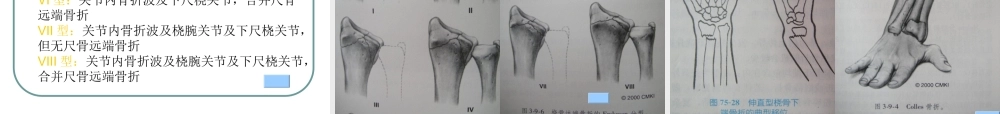

桡骨远端骨折的诊治概述:※桡骨远端骨折是最常见的腕部骨折,占前臂骨折的74%※最常见的损伤机制是过伸位跌倒并伸手支撑※通过腕部触诊和X线可以做出骨折的诊断※虽然有好几种分类方法可用来鉴别腕部骨折,但最常用的是AO/ASIF和Frykman分型※大多数骨折首选的治疗是闭合复位或外固定。如果骨折无法复位,必须切开复位。腕部的解剖:(1)8块腕骨(2)2根前臂骨尺倾角与掌倾角桡骨下端关节面呈由背侧向掌侧、由桡侧向尺侧的凹面、分别形成掌倾角(10°~15°)和尺倾角(20°~25°)定义:桡骨远端骨折是指距桡骨远端关节面3cm以内的骨折。●该部位是松质骨与密质骨的交界处,为解剖薄弱处,一旦遭受外力,容易骨折。其发病率约占急诊骨折病人的17%,其中关节内骨折占桡骨远端骨折的25%。桡骨远端骨折主要发生在青少年和中老年两个年龄段。在青少年,男性发病率显著高于女性,与患者户外活动及骨骼发育有关,主要是高能量损伤引起;在中老年,女性患者明显多于男性,随着年龄增加,其发生率逐步上升,低能跌伤远比高能创伤多,其原因与高龄及女性绝经后的骨质疏松相关。病因与分类病因多为间接暴力引起最常见的损伤机制是跌倒时手过伸支撑其次是运动相关损伤和交通事故骨质疏松是老年人桡骨远端骨折多发的重要因素分型※桡骨远端骨折的分类方法很多,但几乎所有的分类都是以受伤机制和骨折形态为依据,没有哪一种分类方法能包括所有的骨折情况。临床最常用的分类方法有以人名命名的方法和AO分类方法。主要介绍AO/ASIF分类系统。(1)A0/ASIF将桡骨远端骨折分为27类。将桡骨远端骨折分为关节外骨折(A型)、部分关节内骨折(B型)及复杂关节内骨折(C型)3种基本类型。每型再分成3组:A型关节外骨折:A1孤立的尺骨远端骨折,A2桡骨远端骨折、无粉碎、嵌插,A3桡骨远端骨折、粉碎、嵌插;B型简单关节内骨折:B1桡骨远端矢状面骨折,B2桡骨远端背侧缘骨折,B3桡骨远端掌侧缘骨折;C型复杂关节内骨折:C1关节内简单骨折(2块),无干骺端粉碎,C2关节内简单骨折(2块),合并干骺端粉碎,C3粉碎的关节内骨折。附加尺骨损伤,可产生多种桡骨远端骨折的组合型式。AO分型是目前公认的较全面实用的分型方法,对选择手术入路和固定方式及判断预后具有重要指导意义。骨折AO分类由5位诊断数码组成,前两位表示部位,后三位表示形态特点部位编码:1肱骨,2尺桡骨,3股骨,4胫腓骨,5脊柱,6骨盆,7手,8足,91.1髌骨,91.2锁骨,91.3肩胛骨,...